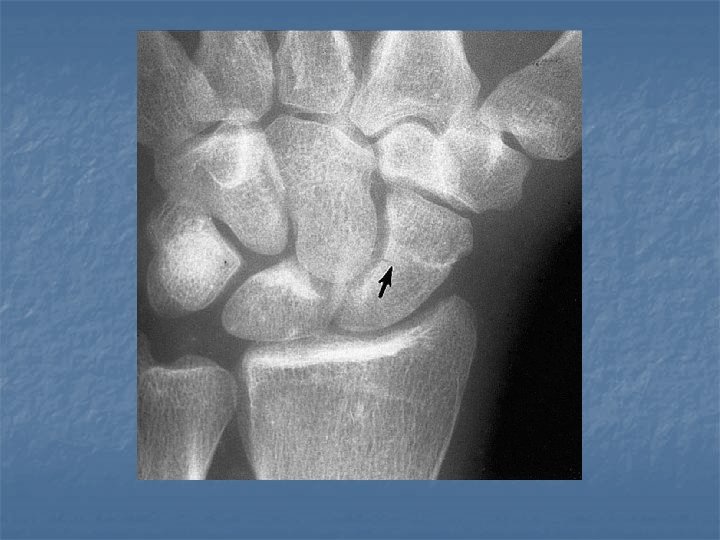

Scapholunate dissociation n n Results from injury of the scapholunate ligament Radiographicaly diagnosed by Terry Thomas sign due to widening of the space between the scaphoid and lunate more than 2 mm

Terry Thomas sign